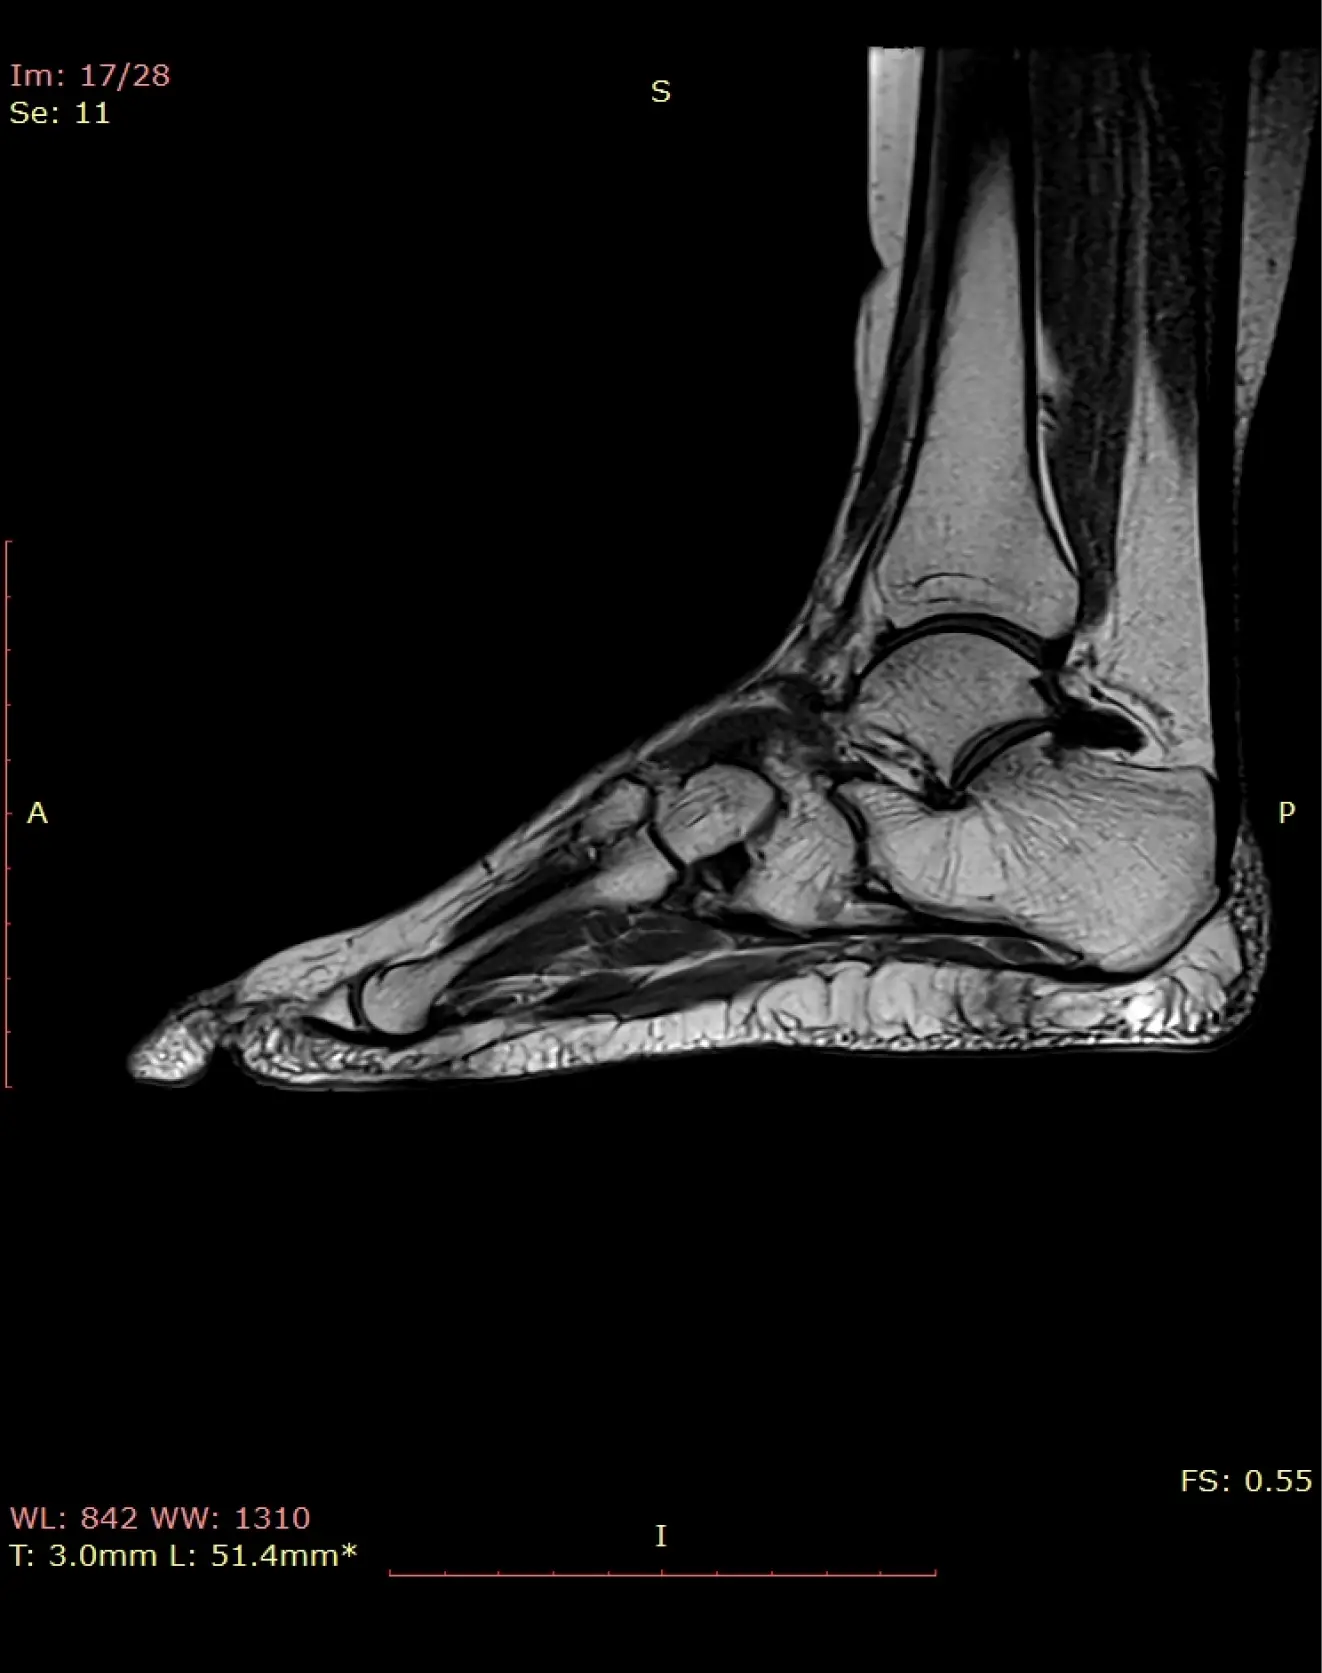

МРТ голеностопного сустава

Визуализация костей голеностопного сустава, сухожилий, связок, регионарных мышц.